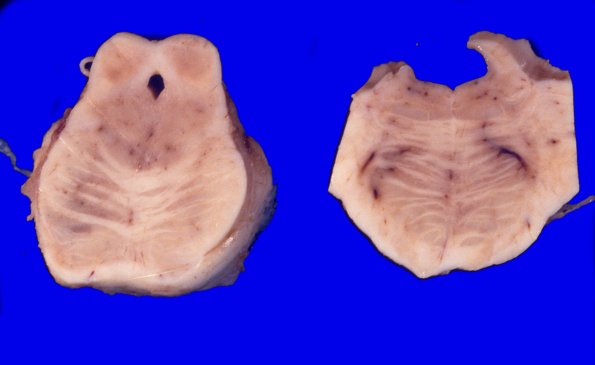

The loci cerulei are pale and the asymmetric cut of the brainstem shown demonstrates discoloration and granularity of the superior colliculus.